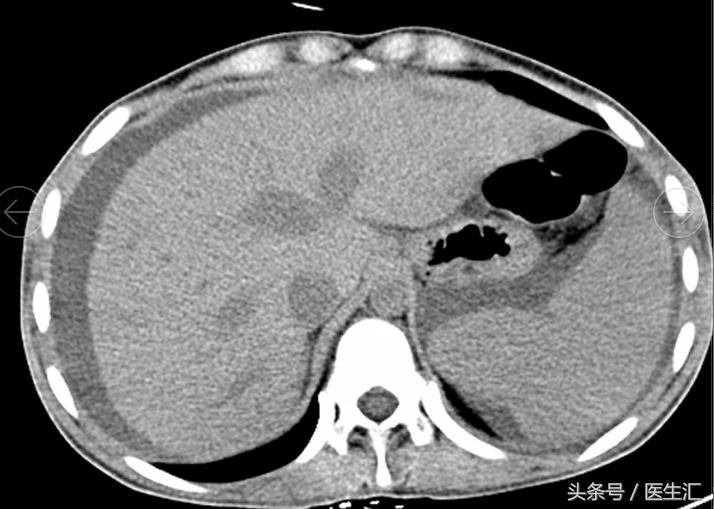

2011-10-24 腹部CT:肝硬化、脾大(9个肋单元);三支肝静脉增宽,未见充盈缺损;下腔静脉未见明显异常;肝内胆管轻度扩张